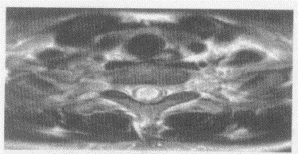

5.患者,男,30歲,兩手乏力、發(fā)麻,結(jié)合圖像,最可能的診斷是

正確答案:A